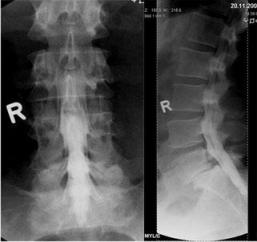

Aufnahmen von der Wirbelsäule zur Beurteilung von Veränderungen am Knochen, vor Operationen, zum Ausschluß von Knochenbrüchen und zur Verlaufskontrolle. Eine spezielle Vorbereitung der Patienten ist nicht notwendig. Moderne Röntgengeräte fertigen solche Aufnahmen mit einer geringen Strahlendosis an. Für alle, die sich genauer über die Auswirkung von Strahlen informieren wollen, empfiehlt sich ein Blick in Wikipedia.

Im Röntgenbild sieht man vergrößerte und deformierte Wirbelgelenke.